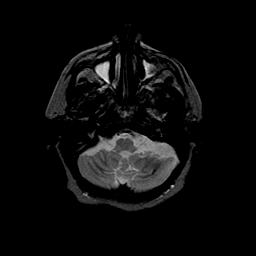

Basal Ganglia Calcification: T2-weighted MR -- Slice #3

[Home][Help][Clinical] Slice 3